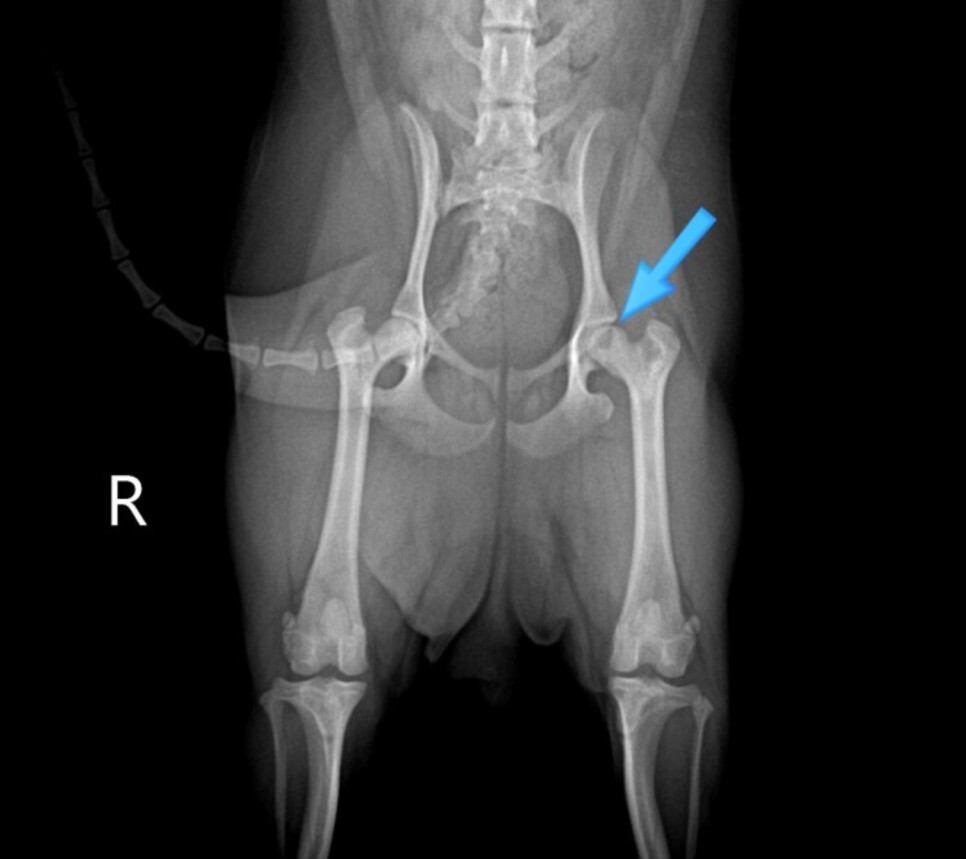

화살표 부분을 보면 뼈 안에 검은색으로 보이는

부분을 확인할 수 있습니다.

검은색으로 보이는 이유는 뼈가

부족하기 때문입니다.

방사선은 뼈를 투과하지 못하기 때문에 하얗게

보이지만 검은색으로 보이는 부분은 다른 부분보다

방사선이 많이 투과하여 어둡게 보이는 것입니다.

신체검사와 방사선 검사 결과를 토대로 고관절

통증에 의한 증상인 것으로 판단하였습니다.